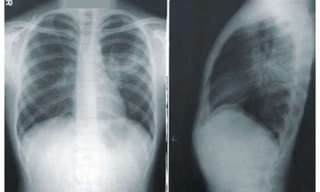

TPO - Bé trai 10 tuổi được chẩn đoán bị viêm phổi nhưng qua nhiều bệnh viện điều trị, tình trạng bệnh vẫn không cải thiện. Tại Bệnh viện Nhi Đồng 2, các bác sĩ phát hiện bệnh nhi bị ung thư phổi hiếm gặp.